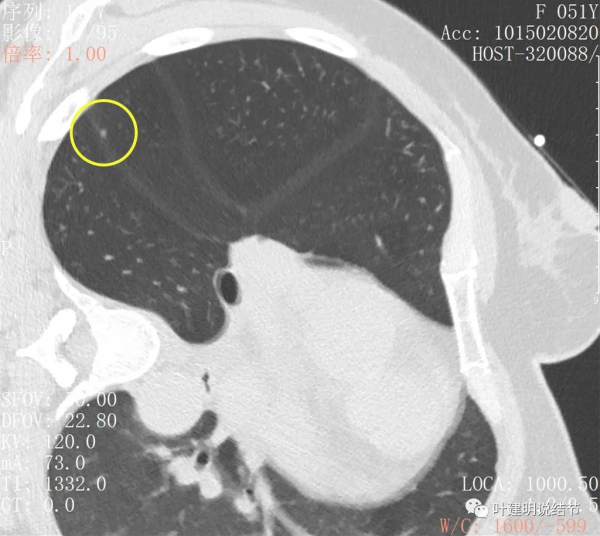

上圖示次病灶(下稱B病灶)仍是顯示淡磨玻璃結節,至多是原位腺癌,以不典型增生可能性為大

上圖示另一次病灶(下稱病灶C),密度偏高,可能是原位腺癌,也可能是微浸潤性腺癌。若單個這樣的病灶不一定惡性,但因為有A與B病灶在,所以這病灶也極可能是惡性的,而若惡性,則因密度較B病灶高,危險性略高於B病灶。

上圖是病灶B,與今年的相比沒什麼大的變化,直徑與密度輪廓均相似,說明病灶較為穩定,相對惰性

上圖是C病灶,也是微小結節,也沒有明顯變化。